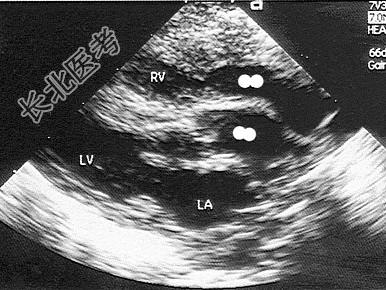

- 单项选择题该病例最可能的诊断为   (   )

A、单心室

B、矫正型大动脉转位

C、右室双出口

D、完全性大动脉转位

E、主动脉骑跨